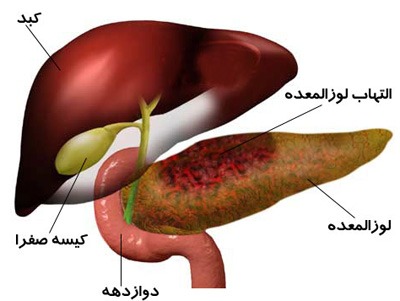

بیشتر بخوانید »بیماری سرطان کیسه صفرا

سرطان کیسه صفرا چیست؟ سرطان کیسه صفرا یک بیماری است که در آن یاخته های بدخیم در بافت های کیسه صفرا دیده می شود. شکل کمیابی از این سرطان، سرطان مقدماتی صفرا است که در لایه میانی کیسه صفرا آغاز می شود و از طریق لایه های خارجی رشد می کند. کیسه صفرا یک عضو کوچک گلابی شکل است …